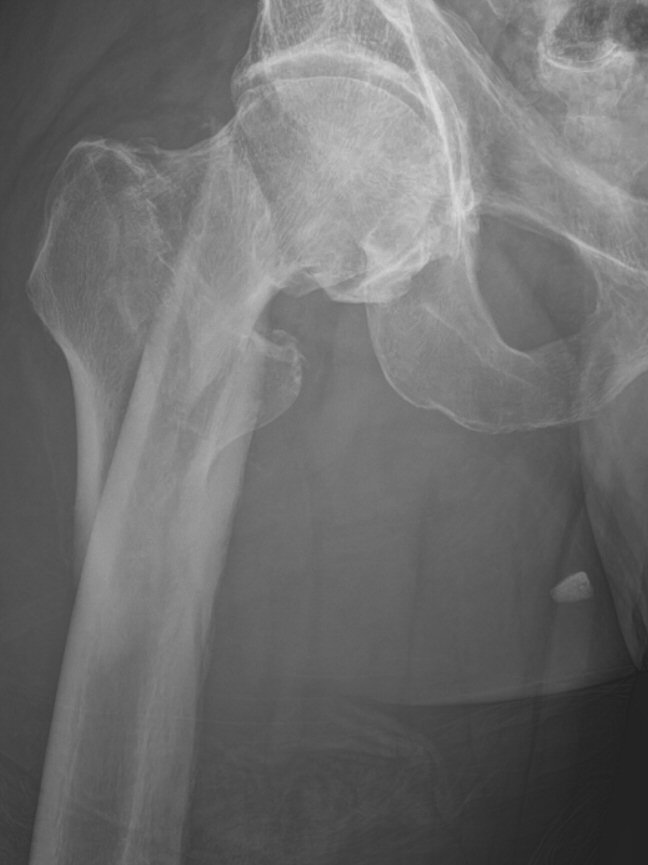

- Pertrokantär femurfraktur (PTFF): fraktur genom trokanterområdet

- Subtrokantär femurfraktur: laterala frakturlinjen går distalt om trokanter minor, ner till max 5 cm distalt om trokanter minor. I AO:s klassifikation finns inte begreppet subtrokantär fraktur, nedanför trokanter minor räknas det som diafysär fraktur.

- PTFF: kort märgspik alt. DHS-platta (om både laterala och mediala väggarna stabila)

- Subtrokantär: lång märgspik